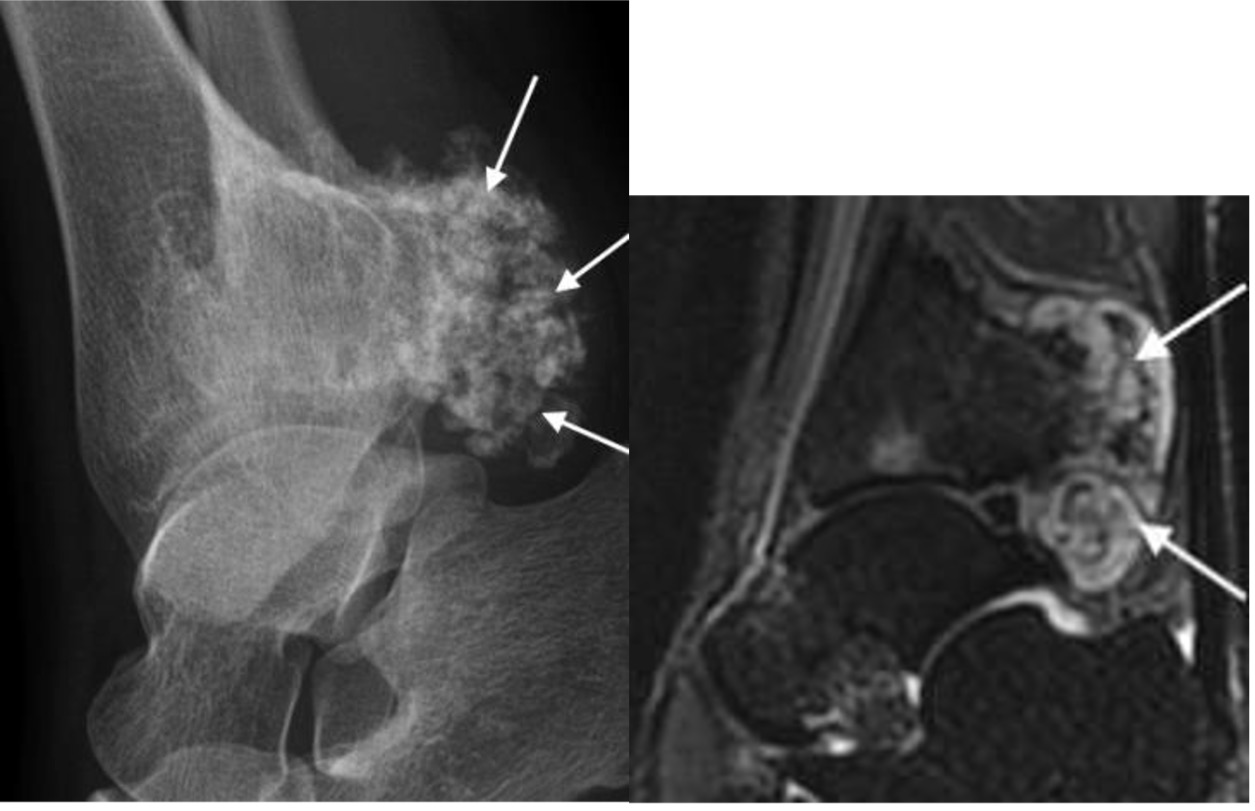

Figure 1. Xray and MRI of synovial sarcoma

Synovial sarcoma

- young to middle aged

- intralesional calcifications in soft tissue mass

- radical surgical excision with wide margins

- 5-year survival ~55%